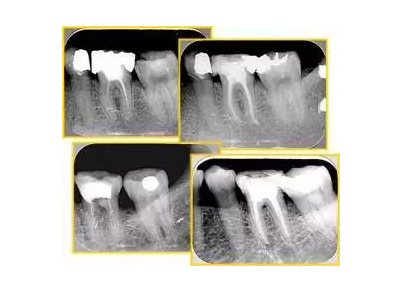

6. 鈣化

常見有修復(fù)性鈣化和增齡性鈣化。下面為根管鈣化 X 線片。

解決方法: ( 1 )清楚根管系統(tǒng)解剖形態(tài)。 ( 2 )安全頭的金剛砂鉆開髓,低速球鉆磨除鈣化牙本( ET20 ,ET40 ,DG-16 )。 ( 3 )徹底去除髓腔周壁的牙本質(zhì)齡。 ( 4 )借助化學(xué)性藥劑,如EDTA 等。

( 5 )初銼選用 8# 或 10#K 銼,平衡力法探察到工作長度 , H銼上下提拉法使根管擴(kuò)大,提高工作效率